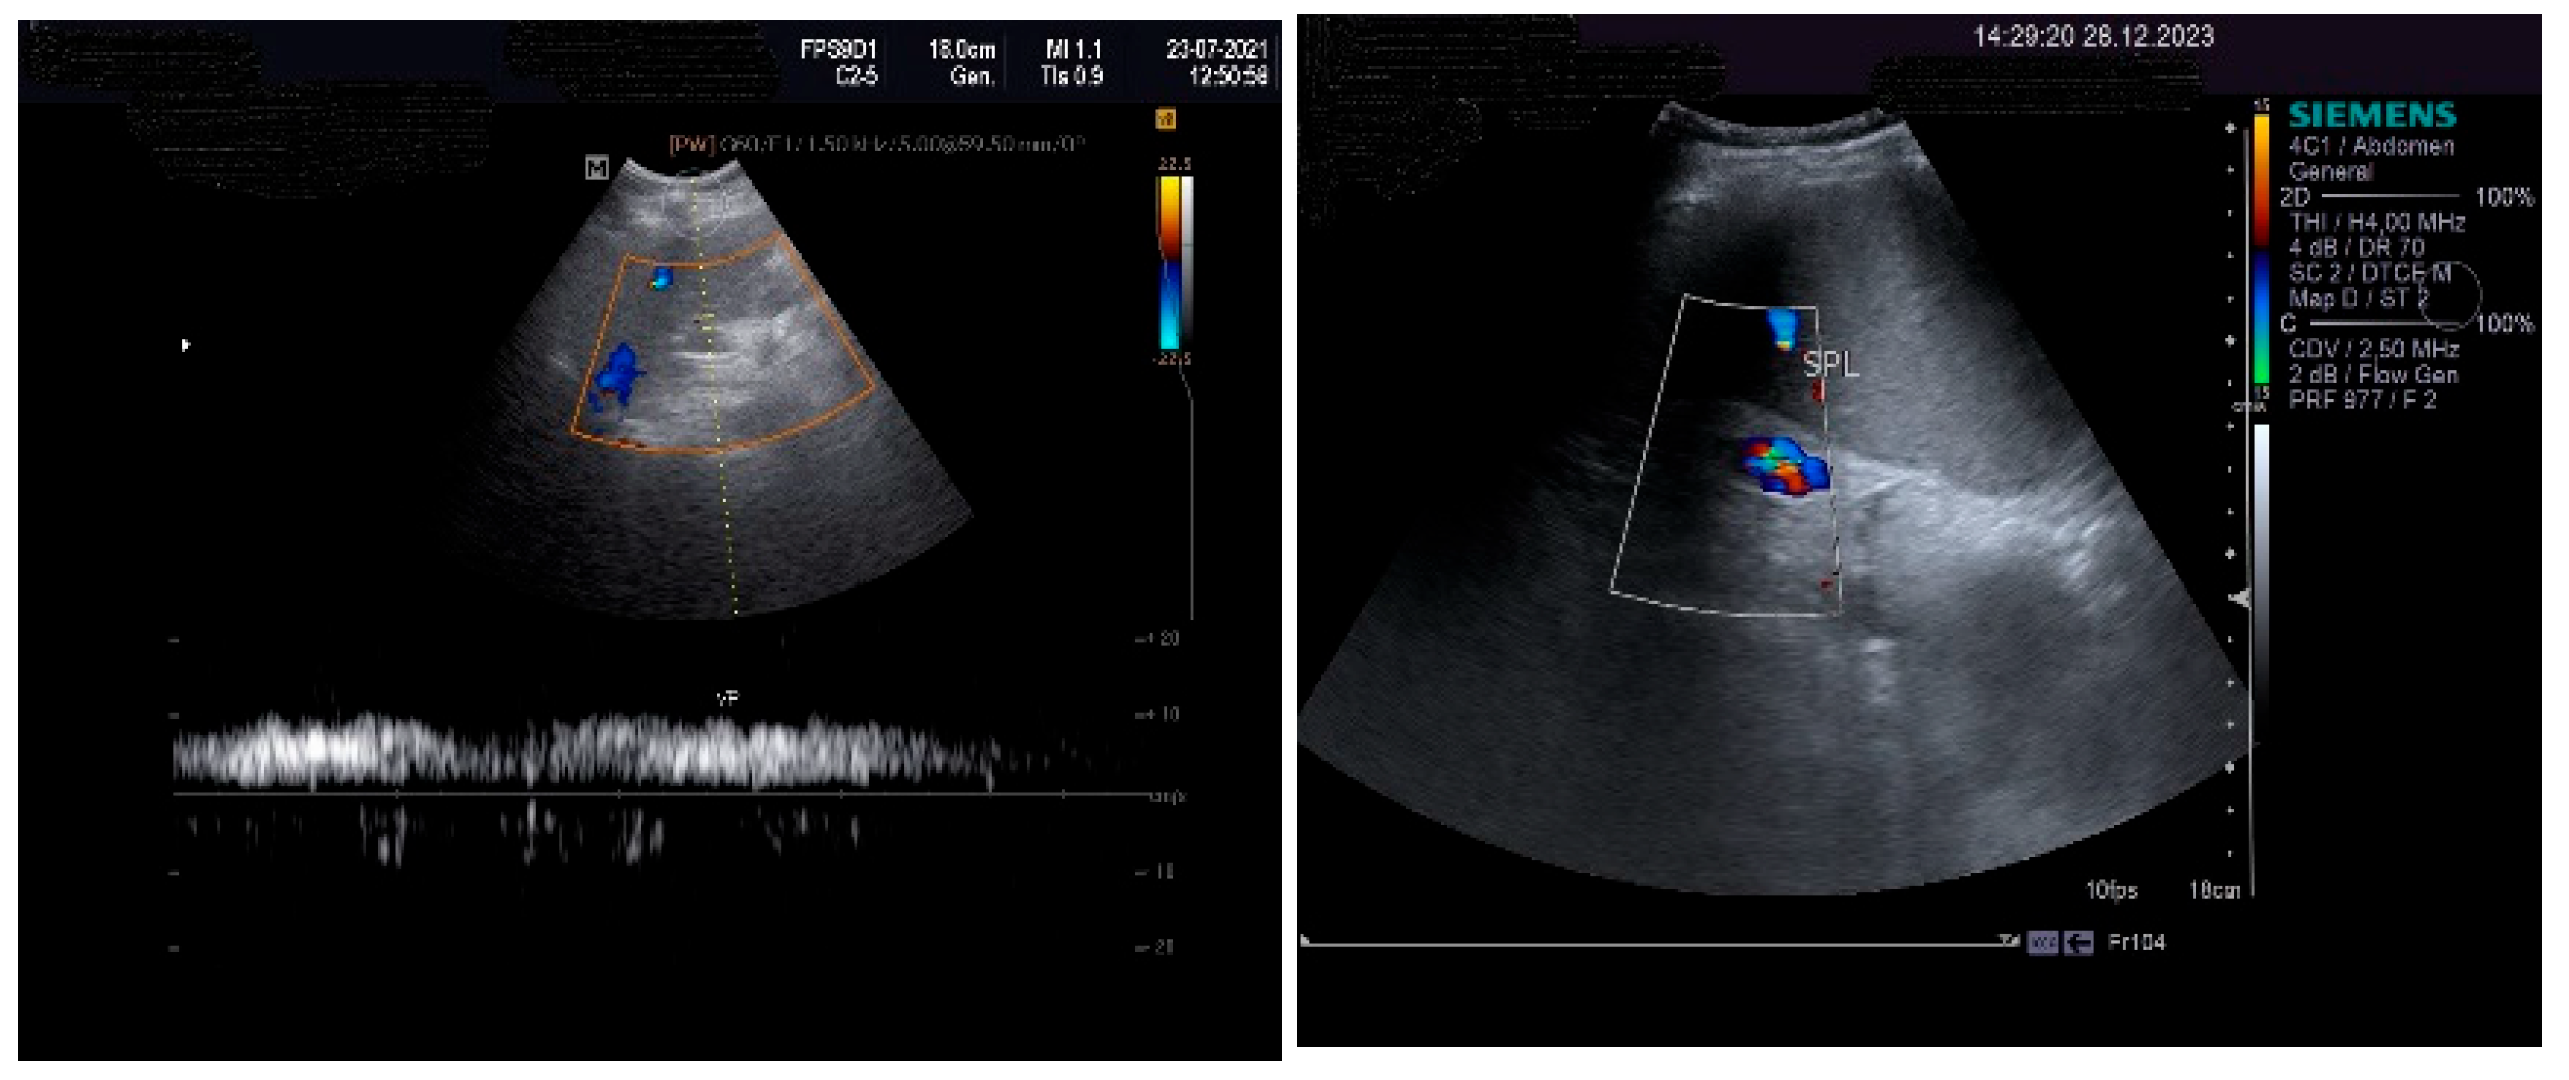

On physical examination, a mild tenderness of the right upper abdominal quadrant, a firm hepatomegaly, a palpable inferior pole of the spleen and a slight increase in abdomen volume were found. No other liver stigmata were noticed. The abdominal duplex ultrasound examination, performed with Siemens high-resolution equipment, showed hepatomegaly with a discrete irregularity of the liver surface, heterogeneity of the liver texture, the caudate lobe at the upper limit, filiform hepatic veins, massive thickening of the gallbladder wall, ascites in small quantity and mild splenomegaly with turbulence of the venous flow in the hilum. The question about liver cirrhosis was asked. Various aspects of the 2D ultrasound examination of the liver are depicted in Figure 2.

The pulsed Doppler ultrasound revealed a patency of the main portal vein as well as of the left and right portal branches and decreased, demodulated hepatopetal portal venous flow, with mildly decreased respiratory variability in the amplitude of the portal vein flow. The Dopler aspects of the liver and spleen are illustrated in Figure 4.

An important role in the imaging diagnostic approach of SOS/VOD is played by ultrasonography. According to some studies, it seems that ascites and gallbladder wall edema represent independent predictors in SOS/VOD diagnosis. Some authors reported that the thickness of the gallbladder wall correlated well with the HVPG. This particular aspect of the markedly thickened GB wall was also observed in the presented patient, associated with ascites and increase in the HVPG. Pulsed Doppler ultrasound is also useful for suggesting SOS/VOD, based on the study of the venous portal flow, which can be decreased or reversed. A significant increase in the HARI may also be associated with liver injury. Hepatic and portal flow anomalies revealed by duplex examination seem to correlate with the HVPG. However, as we have also noted, the reversed portal venous flow is not always recorded and, therefore, one cannot exclude SOS/VOD based on the absence of the hepatofugal portal flow sign [28]. The patient that we have presented in this case report displayed no reversed portal venous flow, but increased values of the HARI.

Figure 4. Doppler examination. Liver: pulsed Doppler of the portal vein (left). Spleen: color Doppler of splenic vein (right).